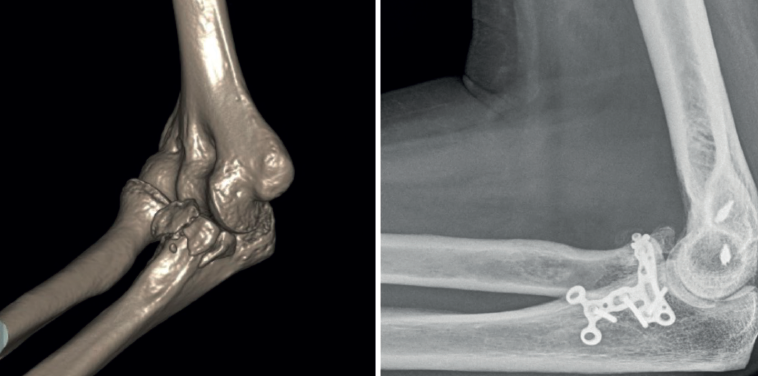

Se han definido 3 patrones de lesión (Tabla 2). Las fracturas de tipo I de O’Driscoll son fracturas que afectan a la punta de la coronoides, están generalmente asociadas con la llamada tríada terrible (fractura de coronoides, fractura de la cabeza del radio y luxación posterior o posterolateral de codo)(5). Suelen acompañarse de rotura del LCL. Las fracturas de tipo II son las que afectan a la faceta AM. Están asociadas con el cuadro de inestabilidad rotatoria posteromedial en varo (VPMRI) y suceden generalmente tras un cuadro de subluxación (no luxación completa)(6). Las lesiones asociadas incluyen la avulsión del LCL del epicóndilo. La cabeza del radio no suele estar afectada. Las fracturas de tipo III son fracturas grandes que afectan al 50% o más de la altura de la coronoides y se asocian con fractura-luxación del olécranon. Las luxaciones por fractura del olécranon anterior presentan una luxación anterior del antebrazo con una articulación radiocubital proximal (RCP) intacta. La fractura de coronoides, en este patrón de tipo III, suele ser un único fragmento grande y los ligamentos suelen permanecer intactos (Figura 3). Se cree que las luxaciones por fractura del olécranon anterior son causadas por un golpe directo en la cara posterior del codo flexionado y con el impacto el húmero pasa a través de la escotadura troclear del cúbito. Las luxaciones por fractura del olécranon posterior se caracterizan por una conminución del olécranon y la apófisis coronoides, un desplazamiento posterior del radio con respecto al capitellum y una fractura de la cabeza del radio. El LCM suele estar intacto en la coronoides fracturada y el LCL sufre una avulsión proximal. Como vemos, en la gran mayoría de los casos tendremos que reparar el LCL, que puede estar afectado en cualquiera de los 3 patrones, además de tratar la fractura de coronoides, así como el resto de las lesiones si lo precisan. Algunos autores defienden que, en fracturas de tipo I y alguna de tipo II con articulación congruente, la reinserción del LCL sin fijación de la fractura de coronoides puede ser suficiente para mantener la estabilidad del codo(7).

- Tipo III. Las fracturas basilares grandes suelen formar parte de una fractura-luxación del olécranon; por tanto, en todos los casos precisarán tratamiento quirúrgico. Podremos sintetizarlas directamente con un tornillo desde la placa posterior de osteosíntesis del cúbito y añadir tornillos interfragmentarios o canulados si es necesario (Figura 6). La reducción de los fragmentos conviene hacerla de forma secuencial, preferiblemente de distal a proximal. A veces precisan una placa medial adicional. Si hay un único fragmento grande, también se pueden fijar con un tornillo insertado de anterior a posterior.